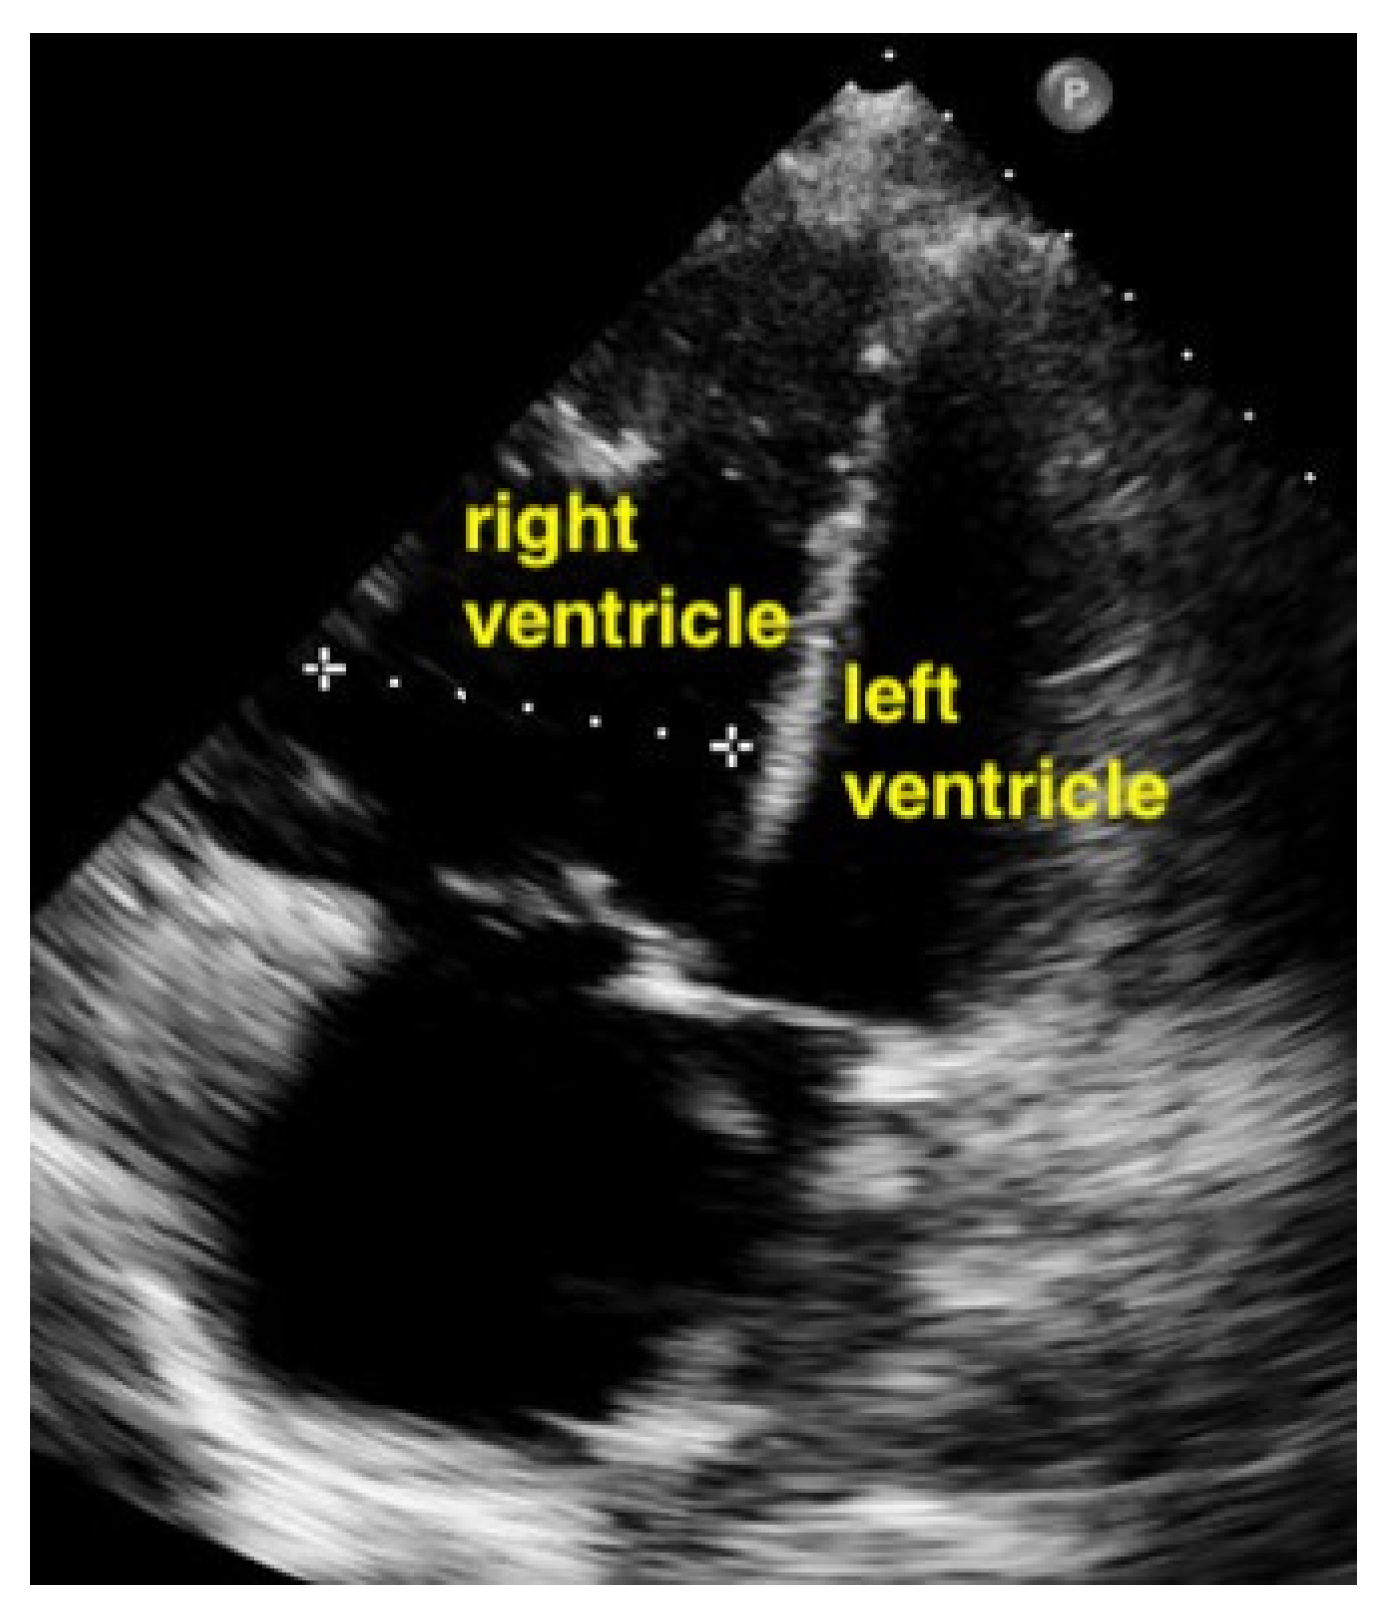

A pulmonary embolism large enough to compromise circulation is typically seen in more centrally located pulmonary arteries, and the subsequent pressure overload results in an enlarged right ventricle. Normally, the right ventricle is slightly smaller than the left ventricle. The size of the right ventricle compared to the left ventricle is best estimated in the apical four-chamber view with a sector probe. However, the subcostal four-chamber view will also reveal an unusually easily seen right ventricle when dilation is present and should be an indication to investigate further. In the case of a central pulmonary embolism, the interventricular septum is typically flattened (apical four-chamber view) and shows a D-sign (parasternal short-axis view) [,] (Figure 15, Figure 16 and Figure 17).

Figure 16.

Parasternal short-axis view. The pathologically increased right ventricular pressure pushes the septum to the left side during diastole, so that a D-shape of the left ventricle results (RV = right ventricle, LV = left ventricle).